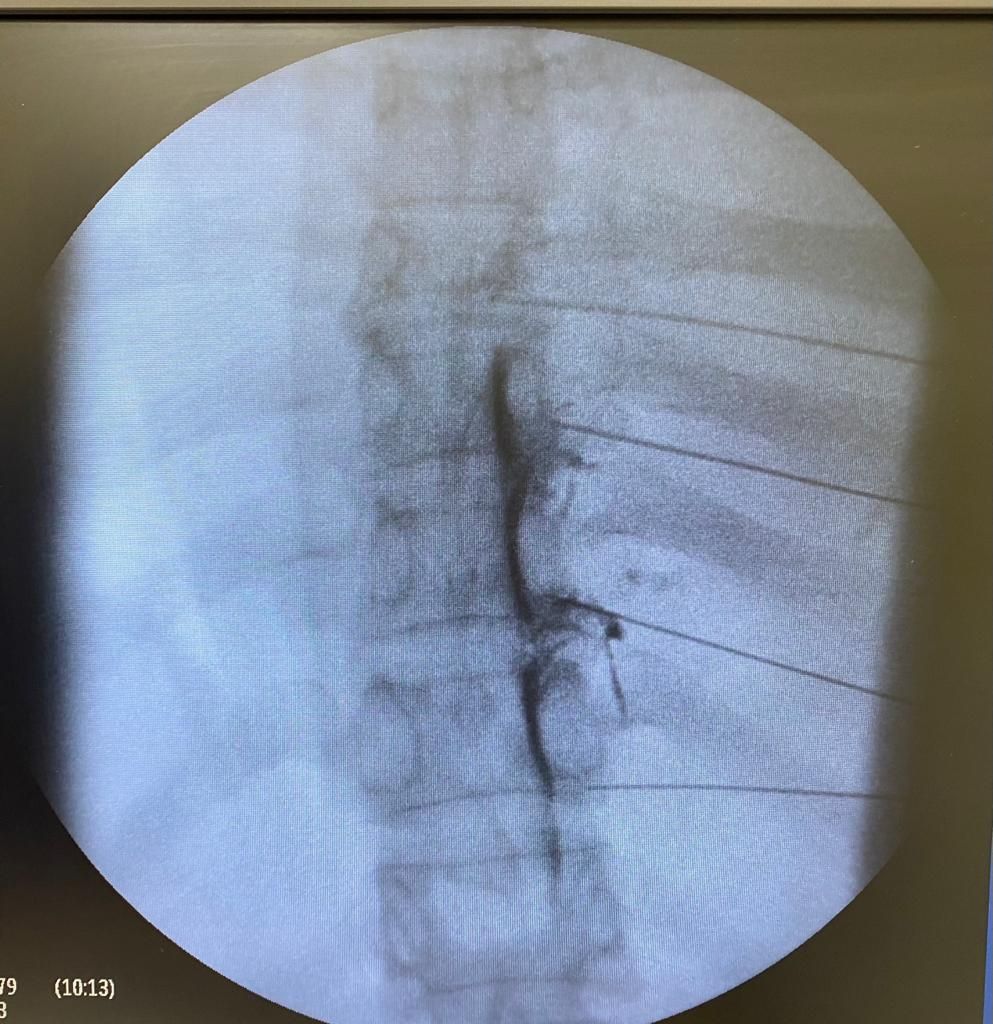

Implante de dispositivos intratecales para manejo de dolor

06/12/2024